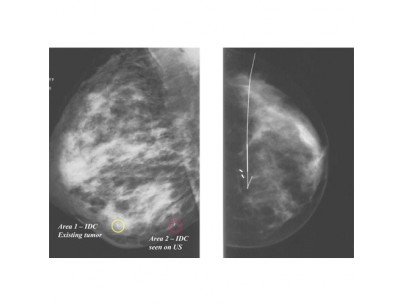

Professionnels de l’imagerie médicale, retrouvez vos consommables et dispositifs médicaux en fonction des examens que vous pratiquez. Vous trouverez des consommables pour biopsie, coloscopie virtuelle, drainage percutané, galactographie, examen vasculaire, thrombectomie TVP ou hystérosalpingographie.